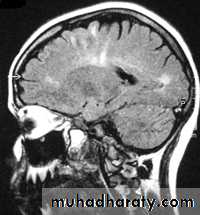

T 2/ FLAIR SEQUENCE: fluid attenuation inversion recoveryT 1w + GADOLINEUM INJECTION / SAGITAL SECTION

Sagital section of brain ( T1 w post contrast injection)

SAGITAL FLUID ATTENUATION INVERSION RECOVERY SEQUENCE: OVOID PLAQUES ( HIGH SIGNAL INTENSITY) , WHICH ARE PERPENDICULAR TO LATERAL VENTRICLE.